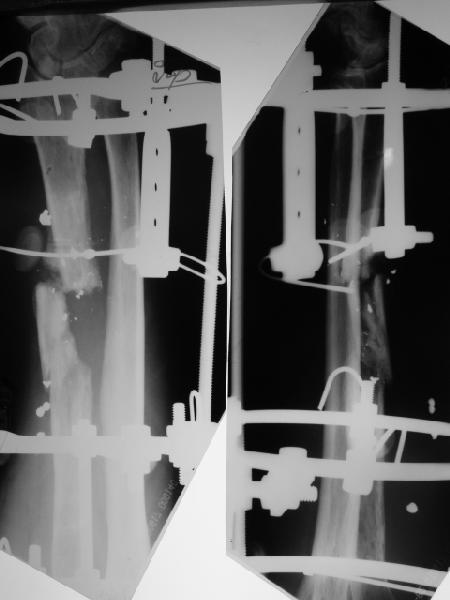

Мужчина 36 лет 5 мес. назад получил дробовое ранение правого предплечья с переломом лучевой кости, повреждением лучевой артерии и срединного нерва.

В больнице по месту жительства обрабатывали рану,сделали несвободную кожную пластику, синтезировали спицей интрамедуллярно, потом убрали. Свищей нет. Линейный рубец по лучевой стороне, приживший лоскут по ладонной (см. картинку).Cращение не произошло (см. снимок).Нейрохирурги что-то надеются сделать, но условием ставят стабилизацию лучевой кости.Какой вариант тут предпочесть? Представляется оптимальным аппаратом дозированно подправить длину и ось, и закрыто ввести интрамедуллярный стержень. Не особо даже рассчитывая на сращение, а только восстановить форму и длину кости, и создать "эндопротез диафиза". Или подумать про какие-то другие варианты?A male 36 years old 5 month ago sustained a gun-shot wound with the radial fracture and lesion of a.radialis and n.medianus. Debridement was performed at the initial hospital, full-thickness skin grafting and intramedullary fixation of the radius by a small wire, which later was removed. No sinuses and signs of infection to date. A linear scar on the radial side and the healed flap (see image). Healing was not reached (see x-rays).Neurosurgeons hope to do something with the peripheral nerves but only in case of stabilization of the radius.Which treatment modality should be preferred? I would perform gradual alignment with the Ilizarov, and perform secondary closed nailing. Even not to expect to reach union, just to restore length andalignment with the "shaft endoprosthesis". Or it is worth to think about other options?

Пока мы наложили аппарат для восстановления оси и длины лучевой кости. Снимок прлагаю.

[ Ответить ]